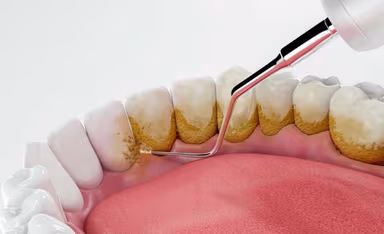

Cao răng dưới nướu thường sẽ được xử lý bằng phương pháp với máy siêu âm

Để đảm bảo vấn đề an toàn và hiệu quả, xử lý cao răng nên được thực hiện tại nha khoa. Tại đây, chúng ta có đầy đủ trang thiết bị và bác sĩ với kiến thức chuyên môn để xử lý tình trạng này. Khi đến nha khoa, quy trình lấy vôi răng ở dưới nướu thường bao gồm các bước sau:

Bước 2: Người bệnh sẽ được thực hiện cạo bỏ vôi răng. Chúng ta có thể sử dụng phương pháp lấy cao răng thông thường, lấy cao răng bằng máy thổi cát, máy siêu âm, … Tuy nhiên, máy siêu âm có lực rung linh hoạt giúp tách mảng bám cao răng một cách hiệu quả mà không gây ra cảm giác ê buốt hay đau nhức. Do đó với trường hợp cao răng dưới nướu, phương pháp sử dụng máy siêu âm sẽ thường được lựa chọn.